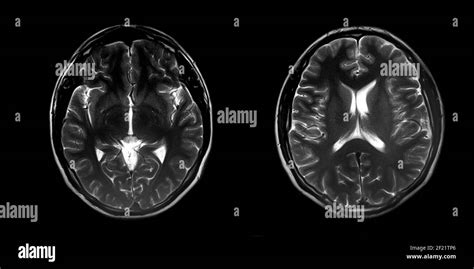

La patologia autistica è complessa e la sua piena comprensione richiederà ancora diversi anni. Tuttavia, sempre più ricerche ipotizzano che alla base dell'autismo vi sia una differenza morfologica nella corteccia cerebrale. Il disturbo dello spettro autistico, di cui oggi si celebra la giornata mondiale, ha un'origine ancora sconosciuta. Negli ultimi anni, anche grazie allo sviluppo della diagnostica per immagine, la ricerca si è concentrata sulle possibili anomalie nelle relazioni tra le diverse aree della corteccia. I primi riscontri non stanno tardando ad arrivare. Uno studio pubblicato su Brain emerge come nei soggetti autistici le connessioni tra la corteccia visiva e quella prefrontale ventromediale, implicata nello sviluppo delle emozioni, sarebbero notevolmente ridotte, con importanti ripercussioni sui comportamenti sociali. Gli autori della ricerca sono giunti a questa conclusione dopo aver sottoposto poco meno di mille persone, autistiche (523) e non (452), a una risonanza magnetica funzionale (fMRI) in grado di svelare le connessioni profonde presenti tra le quasi cinquantamila aree cerebrali osservate. Un'analisi approfondita che ha permesso di svelare nel dettaglio l'anatomia dei rapporti tra le diverse porzioni della corteccia, da cui è stato sviluppato un set di dati per i cervelli degli autistici e dei "controlli" inseriti nello studio. Secondo gli autori, questo approccio, se validato, potrebbe essere utile anche nell'analisi di altri disturbi cognitivi, dall'ossessivo-compulsivo all'iperattività, fino alla schizofrenia. Per ora, la ricerca punta a cercare nuove conferme nel campo delle alterazioni dell'anatomia cerebrale, da cui sono giunte le più recenti evidenze.

L'autismo è un disturbo neurobiologico dello sviluppo che si manifesta durante i primi tre o quattro anni di vita e perdura per tutto il ciclo vitale. Comporta principalmente deficit nella condotta, ma numerose ricerche hanno dimostrato che il problema ha origine nello sviluppo neurale del feto. Alcuni ricercatori hanno individuato una relazione tra il grado di eccessiva crescita del cervello e la gravità dei sintomi dell'autismo. Infatti, è stato dimostrato, attraverso studi di risonanza magnetica strutturale, che la crescita eccessiva del cervello del bambino con autismo inizia durante il primo anno di vita, o anche prima (Amaral et al., 2017; Kessler, Seymour e Rippon, 2016).

Utilizzando la risonanza magnetica funzionale, una tecnica di neuroimmagine totalmente non invasiva che permette di ricostruire digitalmente il cervello dei pazienti in tre dimensioni, i ricercatori IIT hanno analizzato le scansioni cerebrali di 30 bambini affetti da disturbi dello spettro autistico, tutti portatori della stessa mutazione genetica nota come "delezione 16p11.2". Lo studio ha previsto una ricerca parallela su modelli animali in cui è stata riprodotta la mutazione 16p11.2. Sempre grazie alla risonanza magnetica, anche nelle cavie sono stati riscontrati gli stessi deficit di connettività e una riduzione del dialogo tra le medesime aree corticali come nei bambini affetti da autismo. I ricercatori dell'Università di Pisa hanno poi studiato il cervello dei topi portatori della delezione 16p11.2 per cercare di capire se vi fossero alterazioni strutturali capaci di spiegare i deficit di connettività funzionale osservati. Alla luce di questi risultati, i ricercatori stanno ora studiando altri geni per comprendere come le mutazioni nel DNA associate all'autismo alterino le funzioni cerebrali e per individuare le diverse categorie che compongono lo spettro dell'autismo. "Ci aspettiamo che questo tipo di approccio permetta di identificare in maniera oggettiva quante e quali forme di autismo esistano," conclude Alessandro Gozzi, "un prerequisito fondamentale per l'identificazione di future terapie mirate."

Sebbene i disturbi dello spettro autistico siano tra i più importanti e studiati disordini dello sviluppo del cervello, la comunità scientifica non è ancora riuscita a fare piena luce sulle cause, né sul modo in cui si presentano a livello biologico. Nel nuovo studio, il team di ricercatori, di cui fa parte anche Alessandro Bertolino del Dipartimento di scienze mediche di base, neuroscienze e organi di senso dell'Università di Bari, ha utilizzato la risonanza magnetica funzionale (fMRI) per valutare la connettività cerebrale in 841 persone con DSA e 984 controlli. "Servendoci della risonanza magnetica funzionale a riposo siamo riusciti a studiare la sincronizzazione dell'attività neuronale tra le varie aree cerebrali e le sue alterazioni, ovvero la diminuzione o l'aumento di questa sincronizzazione," ha spiegato Bertolino.